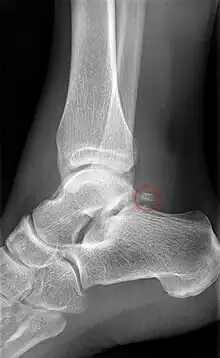

Talusul se vizualizează atât în incidența de față a gleznei[83] sau piciorului,[84] cât și pe cea de profil a gleznei sau piciorului, precum și în incidența oblică pentru articulația talo-calcaneeană.[83][85]

Pe radiografia de față a gleznei se identifică alături de talus și interlinia articulară a gleznei (tibio-fibulo-talară), iar pe cea de profil alături de talus (cu capul, colul și procesul posterior), spațiul articular talo-crural, articulația talo-naviculară,[83] precum și articulația talo-calcaneeană.[84] Tot pe radiografia de profil, se poate observa arhitectura regiunii, remarcându-se continuitatea traveelor osoase din tibie spre talus și calcaneu, iar de aici spre restul plantei.[84]